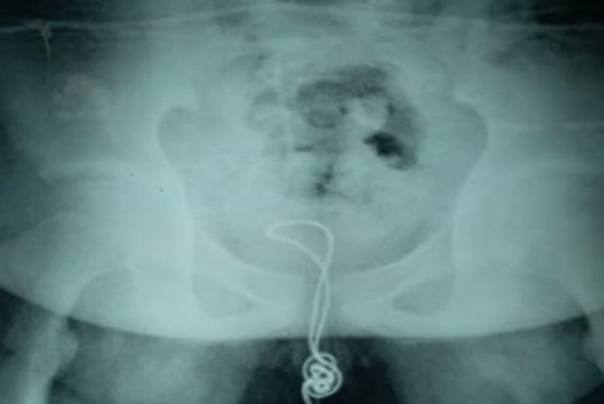

Doktori su uklonili USB kabl iz penisa jednog nemenovanog“ radoznalog“ 13 -godišnjeg tinejdžera iz Kine nakon što ga je ugurao kroz penis – mokraćni kanal … te je ostao zaglavljen u dečakovoj u bešiki.

Nemenovani kineski tinejdžer, ugurao je oko 20 cm kabla u penis pre nego što je shvatio da ne može da ga izvuče napolje , prenosi britanska štampa

Morali su da mu iseku bešiku kako bi pronašli zamršeni kabl, uklonili čvor, a preostali deo izvukli napolje kroz mokraćni kanal, na isti način kako je i ušao unutra.